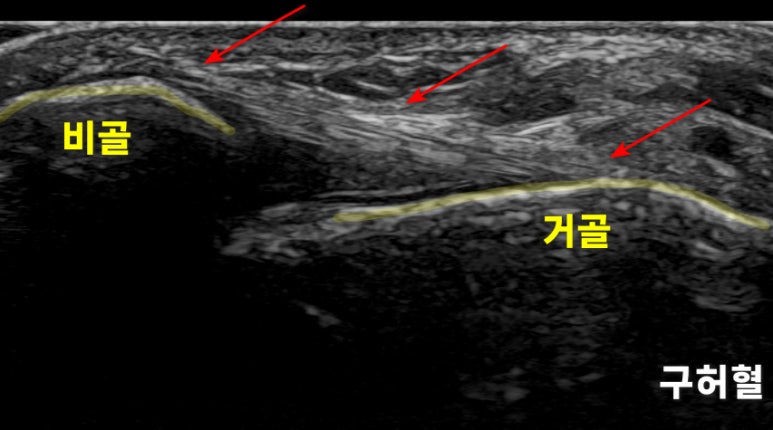

[구허혈]부터

로 체크해봤습니다.

그런데 빨간 화살표로 표시한

인대는 정상적인 형태였습니다.** 이런 경우 전하경비인대 결합과 골간인대를 확인해봐야 하는데요.